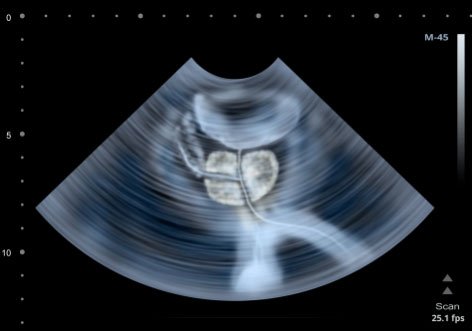

Klinik BPH tanısı için hastanın şikayetleri, klinik muayene ve birtakım tetkikler birlikte değerlendirilerek konulur. BPH tanısı için gerekli olan tetkikler içerisinde idrar testi, PSA, hemogram, böbrek fonksiyon testleri, üroflowmetre ve üriner sistem ultrasonografisi sıklıkla yeterli olmaktadır. İdrar tetkiki ile olası enfeksiyon varlığı, kanama varlığı araştırılır. PSA tetkiki prostat kanseri ve prostat iltihabı tanılarını dışlamak için kullanılan bir kan tetkikidir. Böbrek foksiyon tesleri (üre, kreatinin ve elektrolitler) olası prostat sorununa bağlı böbrek hasarını gösterir. Üroflowmetre işeme akımının hızını göstererek tedavi kararı vermeyi ve tedavi sonrası takipleri yapmayı sağlar. Üriner sistem ultrasonografi ise prostat büyüklüğünü ve eşlik edebilecek taş, tümör, böbrek genişlemesi gibi ek patolojileri ortaya koyar. Ancak tanı karmaşasına yol açan BPH ile ayırıcı tanısı yapılması gereken durumlarda ürodinami, sistoskopi, işeme günlüğü gibi ek değerlendirmeler gerekebilir.